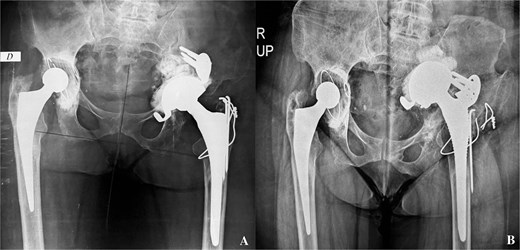

This was a 49-year-old female patient, followed for ankylosing spondylitis, with a history of bilateral total hip arthroplasty. The right side was revised at 13 years post-operative for aseptic loosening of the femoral stem, and the left side was revised at 15 years post-operative for aseptic loosening of the acetabular component. During the latter operation, an acetabular reconstruction with a fragmented bone graft was performed associated to a Kerboull cross-plate (Fig. 1).

A- revision of the left total hip arthroplasty: postoperative pelvis X-ray. B- pelvis X-ray: Intrapelvic migration of acetabular components (Kerboul cross-plate and the cup).

At 4 years post-operative, the patient consulted with left hip pain, walking discomfort and a return to the use of crutches for the past 6 months. On clinical examination, the scar was clean and solid. A lameness of both dodging and discrepancy of lower limbs was observed. Left hip mobility was reduced. Standard radiographs of the pelvis showed intrapelvic migration of a broken Kerboull cross-plate and the acetabular cup. The femoral stem was also loose (Fig. 1). The C-reactive protein was 68 and leukocytes were 11 200. Pelvic angio-CT-scan showed multiple periprosthetic collections. The whole formed a 13x8 cm magma repressing the bladder, sigmoid and uterus and the lateral iliac vessels.